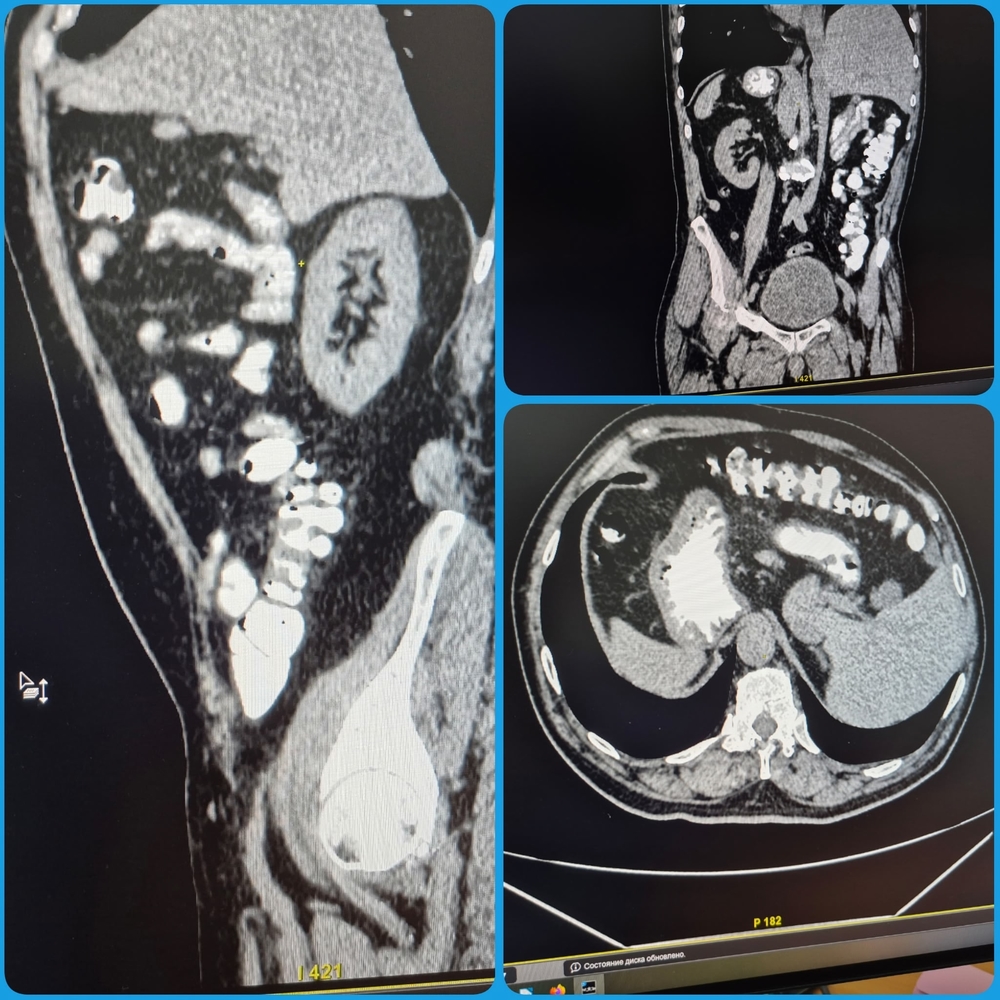

При проведении КТ-обследования брюшной полости и забрюшинного пространства у мужчины был выявлен вариант анатомической нормы, когда все органы пациента располагаются зеркально: печень - слева, сердце - справа, имеется зеркальное отображение аорты и легких.

Такая анатомическая аномалия встречается крайне редко и является признаком "случайной находки" при обследовании. Пациент не знал о наличии у него таких интересных изменений.

"Отмечена полная транспозиция органов. На самочувствии пациента это никак не отражается, ни на что не влияет", - отметила и.о. заведующего рентгенологическим отделением Елена Магомедова.

За 10 лет практики этот врач выявила случай полной транспозиции органов впервые.